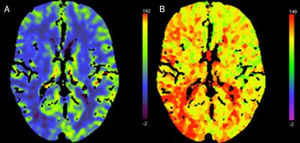

Two patients showed normal perfusion, with no asymmetries in CBV, CBF, or time to peak (Tmax). The most frequent finding in the rest of the sample was longer time to peak (Tmax), with varying CBF and CBV (Figs. 1–3).

Likewise, perfusion CT findings vary depending on when the scan is performed, that is whether the patient is in the ictal, interictal, or postictal period. According to the literature, perfusion CT shows shorter time to peak (TTP/Tmax) and increased CBF and CBV during seizures, which is consistent with hyperaemia,5,7 and longer time to peak (TTP/Tmax) (suggestive of hypoperfusion) in the postictal stage.7,11–14 In the interictal period, perfusion CT reveals longer TTP/Tmax and decreased CBV and CBF, as occurs with vascular events. However, these alterations usually affect more than one vascular territory and are predominantly cortical, with no involvement of the underlying white matter.15 These findings agree with our results.